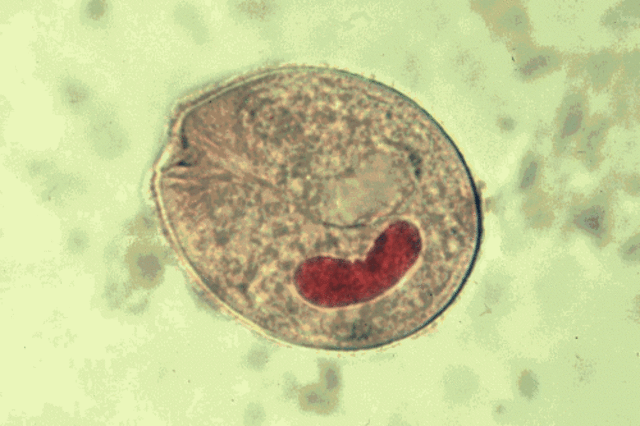

• Protozoos en la Historia

Protozoos en la Historia

Lösch en San Petersburgo, Rusia, identificó Entamoeba histolytica en la materia fecal de una persona enferma de diarrea y demostró la patogenicidad de este protozoo al infectar a un perro.